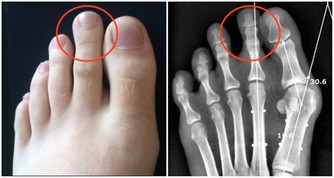

另據研究表明,豆角能顯著降低血清膽固醇的含量,有利於高血壓患者的康復,可作為高血壓患者的保健蔬菜。豆角中還含有效成分能抑制癌細胞的生長,豐富的粗纖維能促進大便的排泄,因此可作為防治腸道癌瘤的食品。